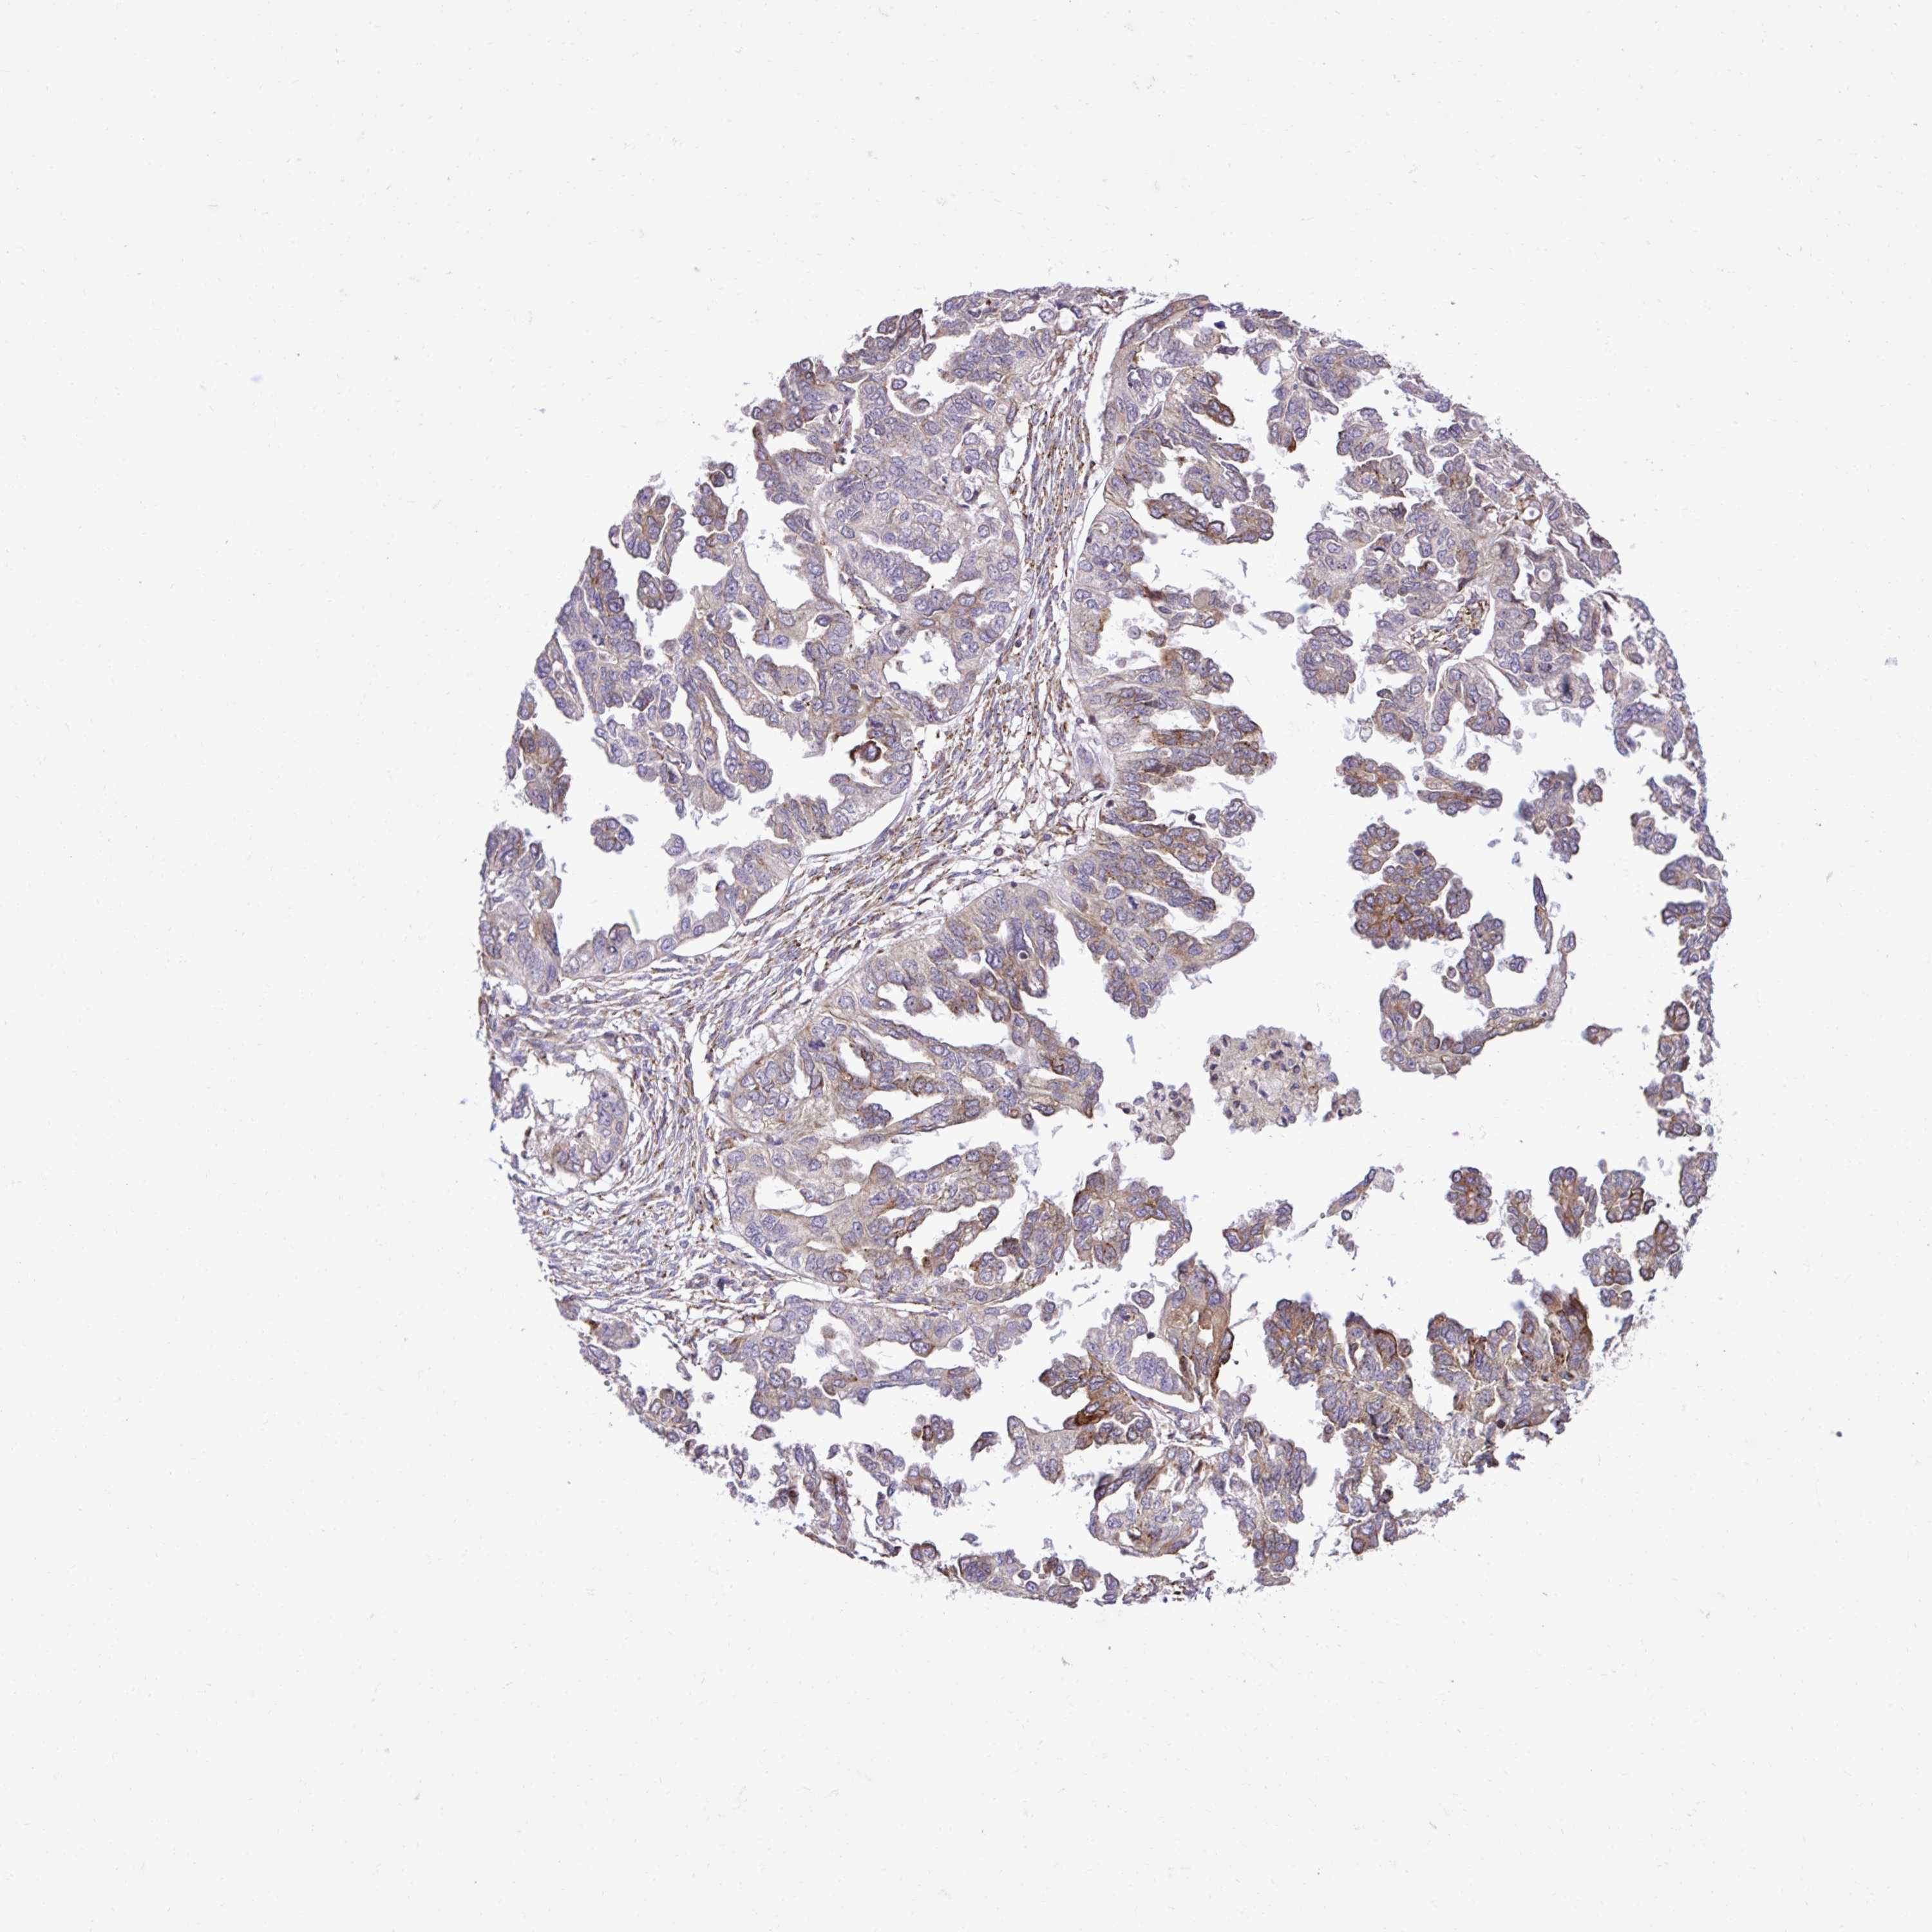

OVARIAN CANCER - Protein expressioni

A mouse-over function shows sample information and annotation data. Click on an image to view it in a full screen mode. Samples can be filtered based on level of antibody staining by selecting one or several of the following categories: high, medium, low and not detected. The assay and annotation is described here.

Note that samples used for immunohistochemistry by the Human Protein Atlas do not correspond to samples in the TCGA dataset.

Antibody stainingi

Antibody staining in the annotated cell types in the current human tissue is reported as not detected, low, medium, or high, based on conventional immunohistochemistry profiling in selected tissues. This score is based on the combination of the staining intensity and fraction of stained cells.

Each image is clickable and will lead to virtual microscopy that enables deeper exploration of all samples and also displays staining intensity scores, fraction scores and subcellular localization as well as patient and tissue information for each sample.

Antibody HPA058455

Antibody HPA061230

Staining

High

Medium

Low

Not detected

Intensity

Strong

Moderate

Weak

Negative

Quantity

>75%

75%-25%

<25%

None

Location

Nuclear

Cytoplasmic/membranous

Cytoplasmic/membranous,nuclear

Cystadenocarcinoma, serous, NOS

Cystadenocarcinoma, mucinous, NOS

Carcinoma, endometroid